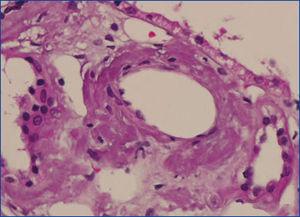

Se decide realizar una biopsia renal, que muestra 26 glomérulos, de los cuales 17 están esclerosados. En algunos de los glomérulos no esclerosados se observan muy focales depósitos nodulares de material hialino eosinófilo, acelular y débilmente ácido peryodico (PAS+) más frecuente en el polo vascular (figura 1), material que se observa también y en mayor cantidad en intersticio y en pared de arterias y arteriolas (figura 2). Este material se tiñe con la técnica de rojo congo (figura 3 y figura 4), tinción que desaparece tras el tratamiento con permanganato, y muestra birrefringencia verde manzana con luz polarizada. Con técnicas de inmunohistoquímica, el material acelular muestra tinción con amiloide A (figura 5). Se observa además una fibrosis intersticial y atrofia tubular moderadas (20 %). Con estos datos histológicos, se realiza el diagnóstico de amiloidosis renal secundaria (AA) con afectación glomerular, vascular e intersticial.

Figura 1. Depósitos de material amiloide en polo vascular y en penacho glomerular con hematoxilina-eosina.